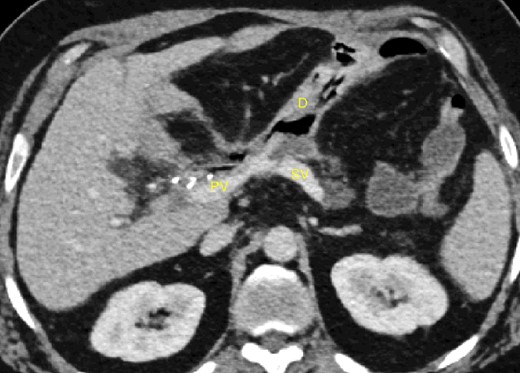

A 52-year-old man with a past medical history of obesity, diabetes, and Lynch syndrome, which had led to a subtotal colectomy 4 years earlier, underwent an open pancreatoduodenectomy for a duodenal adenocarcinoma in the tertiary referral center. The pancreas had a soft texture; hence, a pancreaticogastrostomy anastomosis was performed. No vascular resection or reconstruction was necessary. Multi-tubular drains were placed behind the anastomoses (pancreaticogastrostomy and hepaticojejunostomy) at the end of the procedure. Six days after surgery, the patient developed sepsis due to a pancreatic fistula (grade B, according to ISGPS definition) [4]. The patient was treated with intravenous antibiotics. On the fifteenth postoperative day, we noticed bleeding through the drain orifice (about 400 cc) that stopped spontaneously. The patient was hemodynamically stable, and no active bleeding or arterial pseudoaneurysms were found on a computed tomography (CT) scan. On the twentieth post-operative day, the hemorrhage recurred and ceased spontaneously again. The CT scan showed a splenic vein irregularity without active bleeding or intra-abdominal free fluid (Fig. 1). After a massive new bleeding the same day, we performed an exploratory laparotomy.

20-day post-operative CT scan showing irregularity of the splenic vein, without active bleeding. PV portal vein, SV splenic vein, D multi-tubular drain.